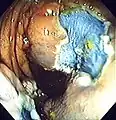

Polyp is identified. A sterile solution is injected under the polyp to lift it away from deeper tissues.

A sterile solution is injected under the polyp to lift it away from deeper tissues. A portion of the polyp is now removed.

A portion of the polyp is now removed. The polyp is fully removed.

The polyp is fully removed.